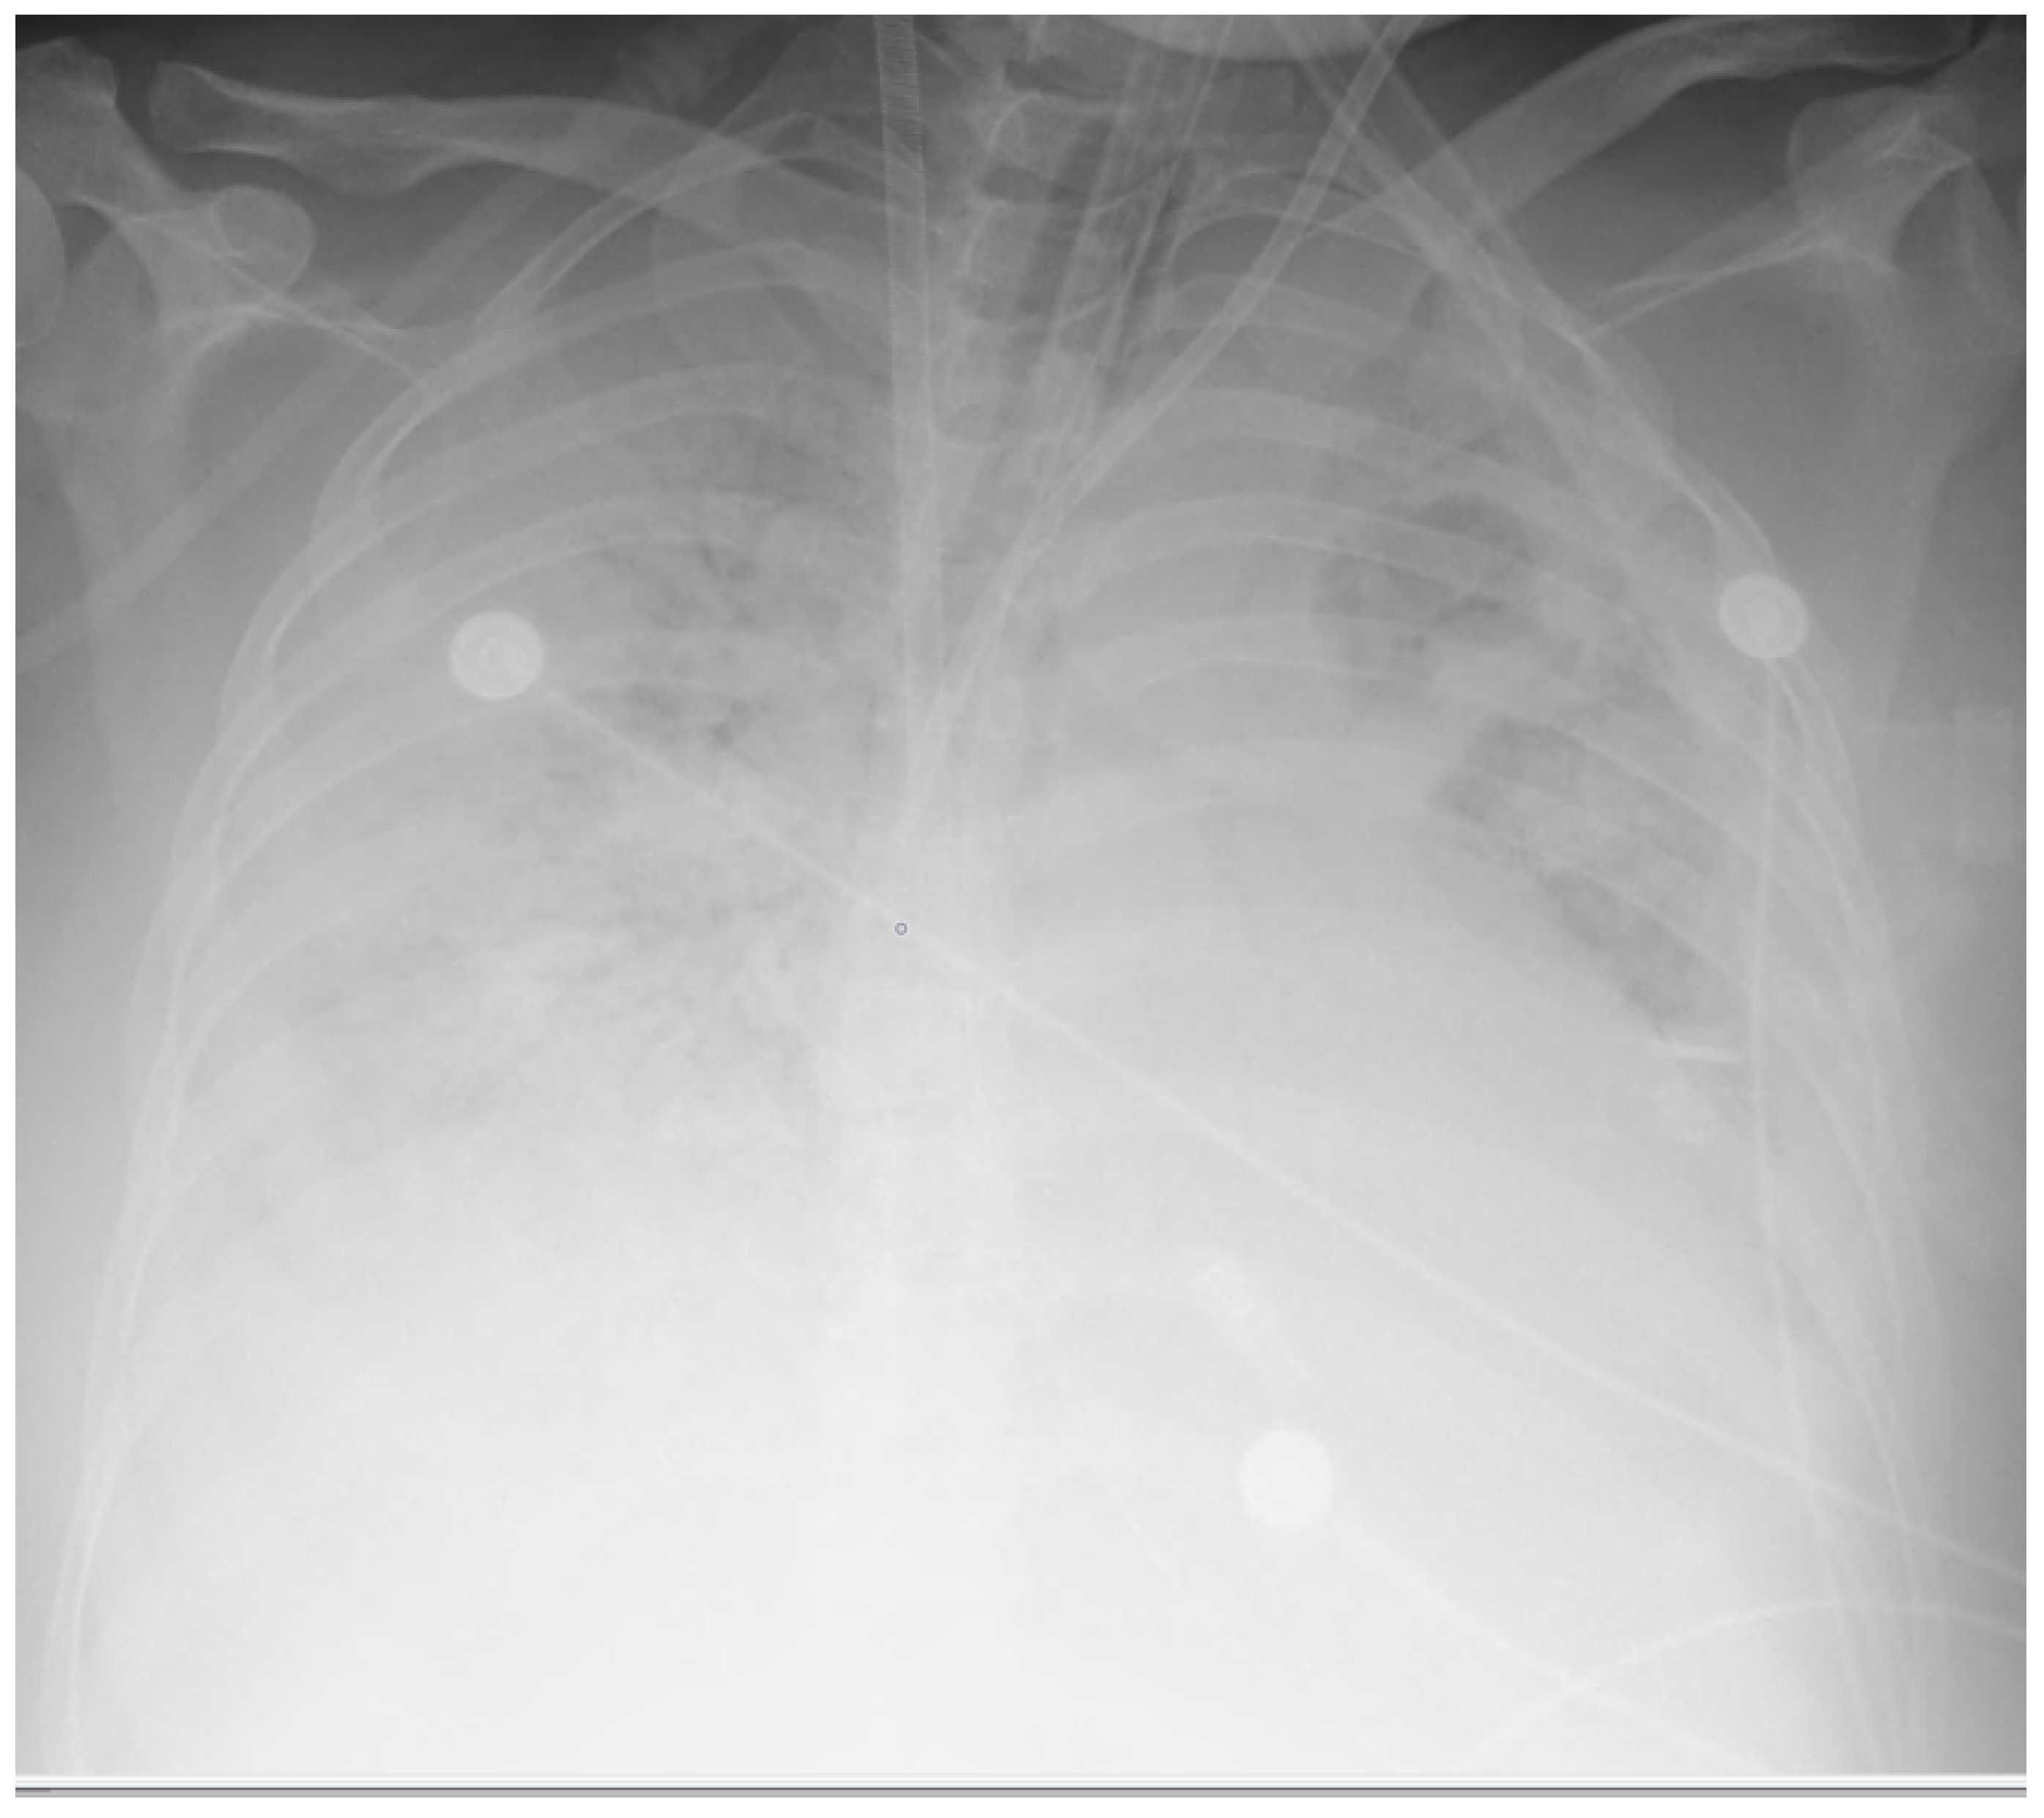

The mean ± SD of the gestational age of all the born babies in this study was 31.43 ± 4.35. The main clinical symptoms on admission to the MICU were dyspnoea, coughing, and fever, which were present in 16 of 19 patients (84.21%). All 19 patients had bilateral infiltrates seen on a chest X-ray (CXR) or computerised tomography (CT) scan, along with a certain degree of ARDS. The most common findings during examination of the chest CT were bilateral diffuse ground glass-like infiltrations and pneumonic consolidation areas. On the chest X-rays, diffuse bilateral infiltration and increased opacity were seen (Figure 1 and Figure 2).

Figure 2. Chest X-ray showing diffuse opacity and infiltrates in a postpartum woman treated with vvECMO.